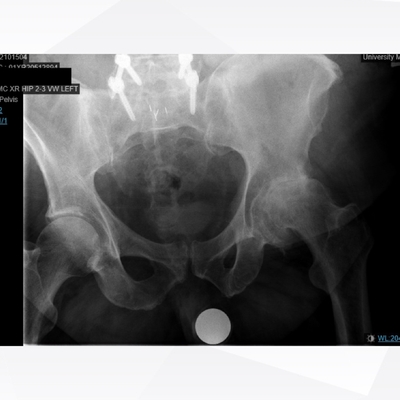

Click on an image below to view more info.